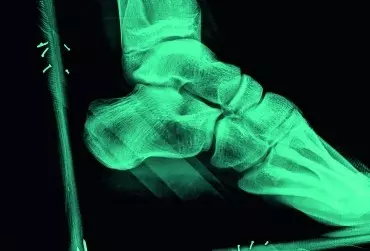

Ludzkie stopy mają ogromne znaczenie w funkcjonowaniu całego organizmu. To na nich spoczywa trud utrzymania ciężaru ciała. Współcześnie nie poświęca się odpowiedniego zainteresowania działaniom profilaktycznym służącym stopom. Odstępstwa od norm są bagatelizowane, a jeśli pojawiają się dolegliwości, zdarza się, że pacjenci liczą na samoistne ich ustąpienie. Refleksja zazwyczaj przychodzi dopiero w momencie, gdy nieprawidłowości przybierają nieodwracalny charakter.

Urazy skrętne stawu skokowego zalicza się do jednych z najczęściej występujących uszkodzeń w obrębie kończyny dolnej, które występują równie często w życiu codziennym, jak i sporcie amatorskim oraz wyczynowym. Statystki mówią, że skręcenia stawu skokowego stanowią 25% przyczyn przerw w aktywności sportowej. W niektórych dyscyplinach odsetek występowania skręceń stawu skokowego jest znacznie większy i sięga 21–53% w koszykówce, a 17–29% w piłce nożnej.